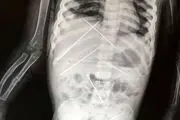

جنایت فروکردن ۷ سوزن داخل بدن دختر۳ ساله!+ عکس

مرد جادوگر با فریب مادر جوان نوعی سحر را روی دختربچه 3 ساله انجام داده بود ، فرورفتن سوزن بدن را در موقعیت خطرناکی قرار داده بود و کار جراح را سخت می کرد.